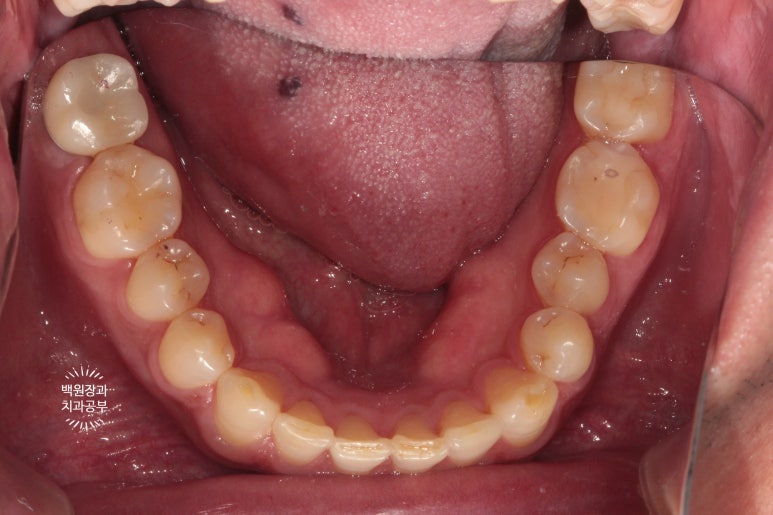

아래턱 치아들을 촬영해 보았습니다.

임플란트 크라운이 거의 자연치아와 유사하게 제작이 되었어요!

저희 신금호역 치과는 모든 임플란트 케이스를 맞춤형 지대주와 지르코니아 크라운을 이용하기에 상당히 훌륭한 결과를 보실 수 있습니다.

위 사진에서 바로 표시해 놓은 이 치아들이 스트라우만 임플란트에 접착한 지르코니아 임플란트 크라운 입니다!

아주 예쁘게 제작이 잘 되었네요!